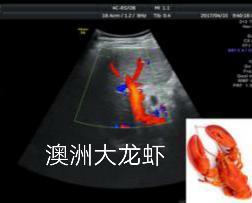

这是一幅肝脏的彩色血流图,鲜红的血流恰似一只完美的澳洲大龙虾,生动形象。大龙虾雄赳赳地举着两只大钳子,通体闪耀着鲜艳的大红色,似乎在告诉大家我的肝脏可是很强壮的哦。